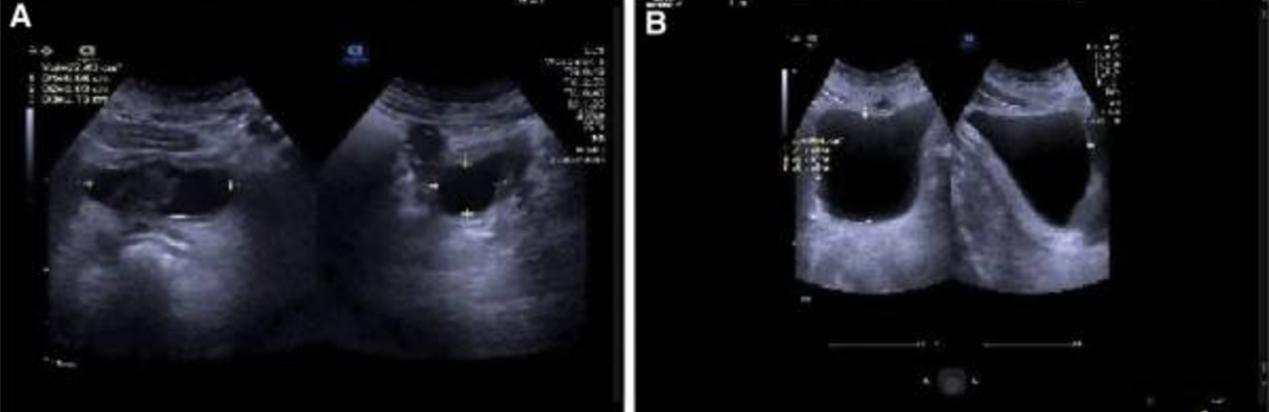

在电针治疗的前3周,患者出现了短暂的尿路感染,可能是由于他长时间的尿潴留,在没有抗菌治疗的情况下自行缓解。经过9周的治疗,患者感觉排尿有力,排气和排便比治疗前流畅,会阴周围的皮肤感觉逐渐恢复。2022年9月22日,膀胱残余尿液27mL(图3A)。然而在移除尿管后再次出现尿潴留,超声检查显示残余尿量为166 mL(图3B)。在门诊继续接受了3周的电针治疗。在随后的治疗结束时,已经完全康复,排尿后无残余尿液(图4)。

图3 A.2022年9月22日,膀胱残余尿液的随访超声显示排尿后膀胱中残留的尿液27mL

B.移除尿管后再次出现尿潴留,超声检查显示残余尿量为166 mL